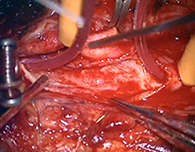

<手術所見>

手術で血管の内部で肥厚した内膜を除去する(内膜剥離術)。

<実際の手術>

頭皮の血管を脳表の血管に吻合する。